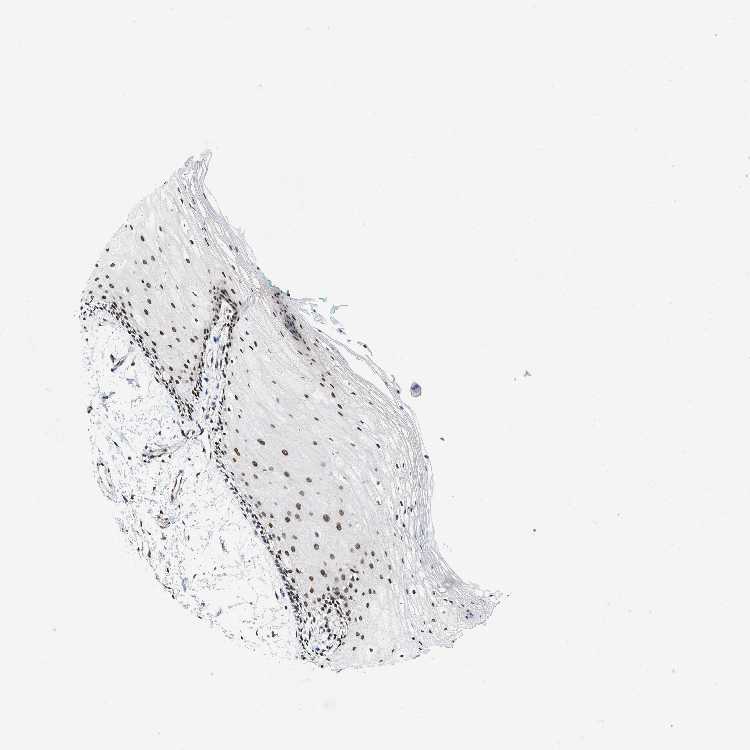

TISSUE PRIMARY DATA ORAL MUCOSA Show tissue menu

ORAL MUCOSA - Antibody stainingi

Antibody staining in the annotated cell types in the current human tissue is reported as not detected, low, medium, or high, based on conventional immunohistochemistry profiling in selected tissues. This score is based on the combination of the staining intensity and fraction of stained cells.

Each image is clickable and will lead to virtual microscopy that enables deeper exploration of all samples and also displays staining intensity scores, fraction scores and subcellular localization as well as patient and tissue information for each sample.

Antibody HPA016832Antibody HPA020076Antibody CAB001969

Squamous epithelial cells HighHighHigh